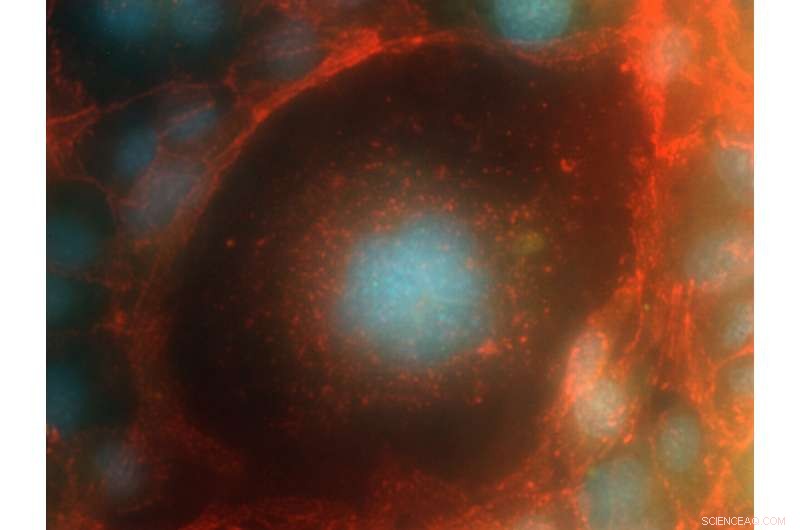

Credit: Ivana Barravecchia, Debora Angeloni, Institute of Life Sciences, Scuola Superiore Sant’Anna, Pisa, Italy

A human endothelial cell that was flown to the International Space Station and returned to Earth for analysis is helping researchers keep astronauts healthy in space.

For the curious, the image shows human capillary endothelial cells HMEC-1, red: b-catenin, blue: nuclei, using a Fluorescence Zeiss PALM MicroBeam Microscope at 63x magnification.